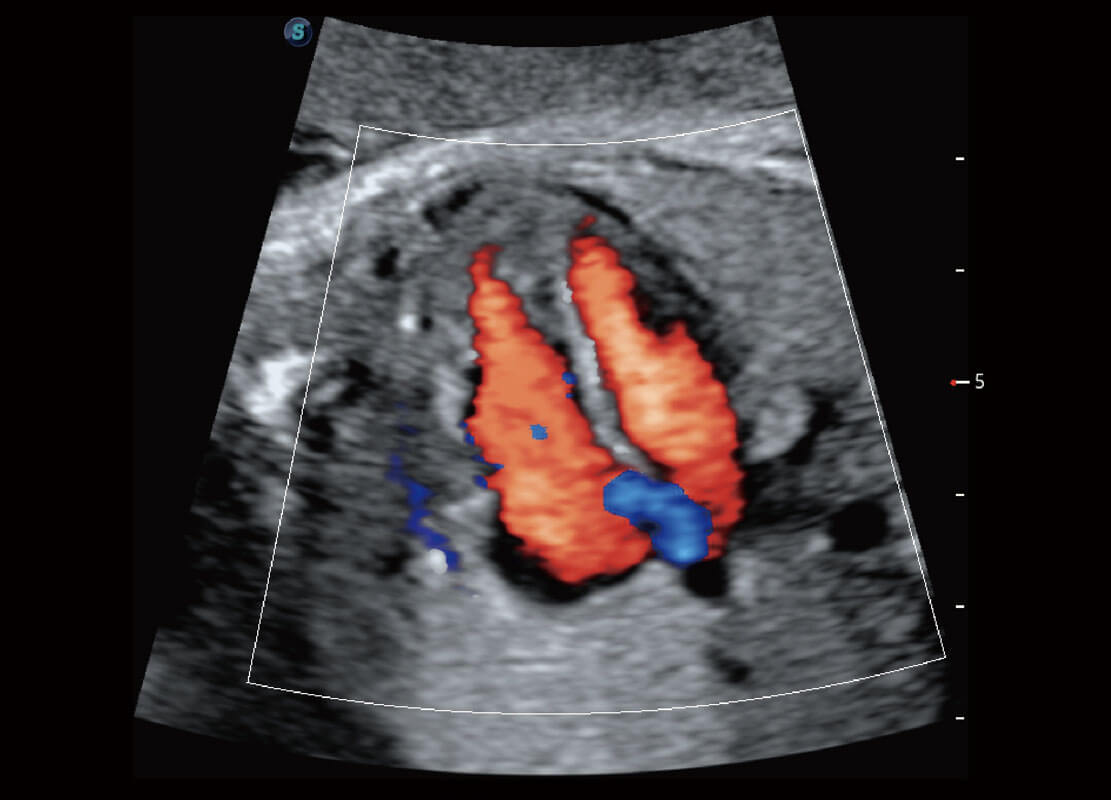

胎儿体循环

P60搭载一系列胎儿心脏成像技术,实现精细的胎儿心脏评估。

四腔切面

四腔心血流

右室双出口

胎心容积成像